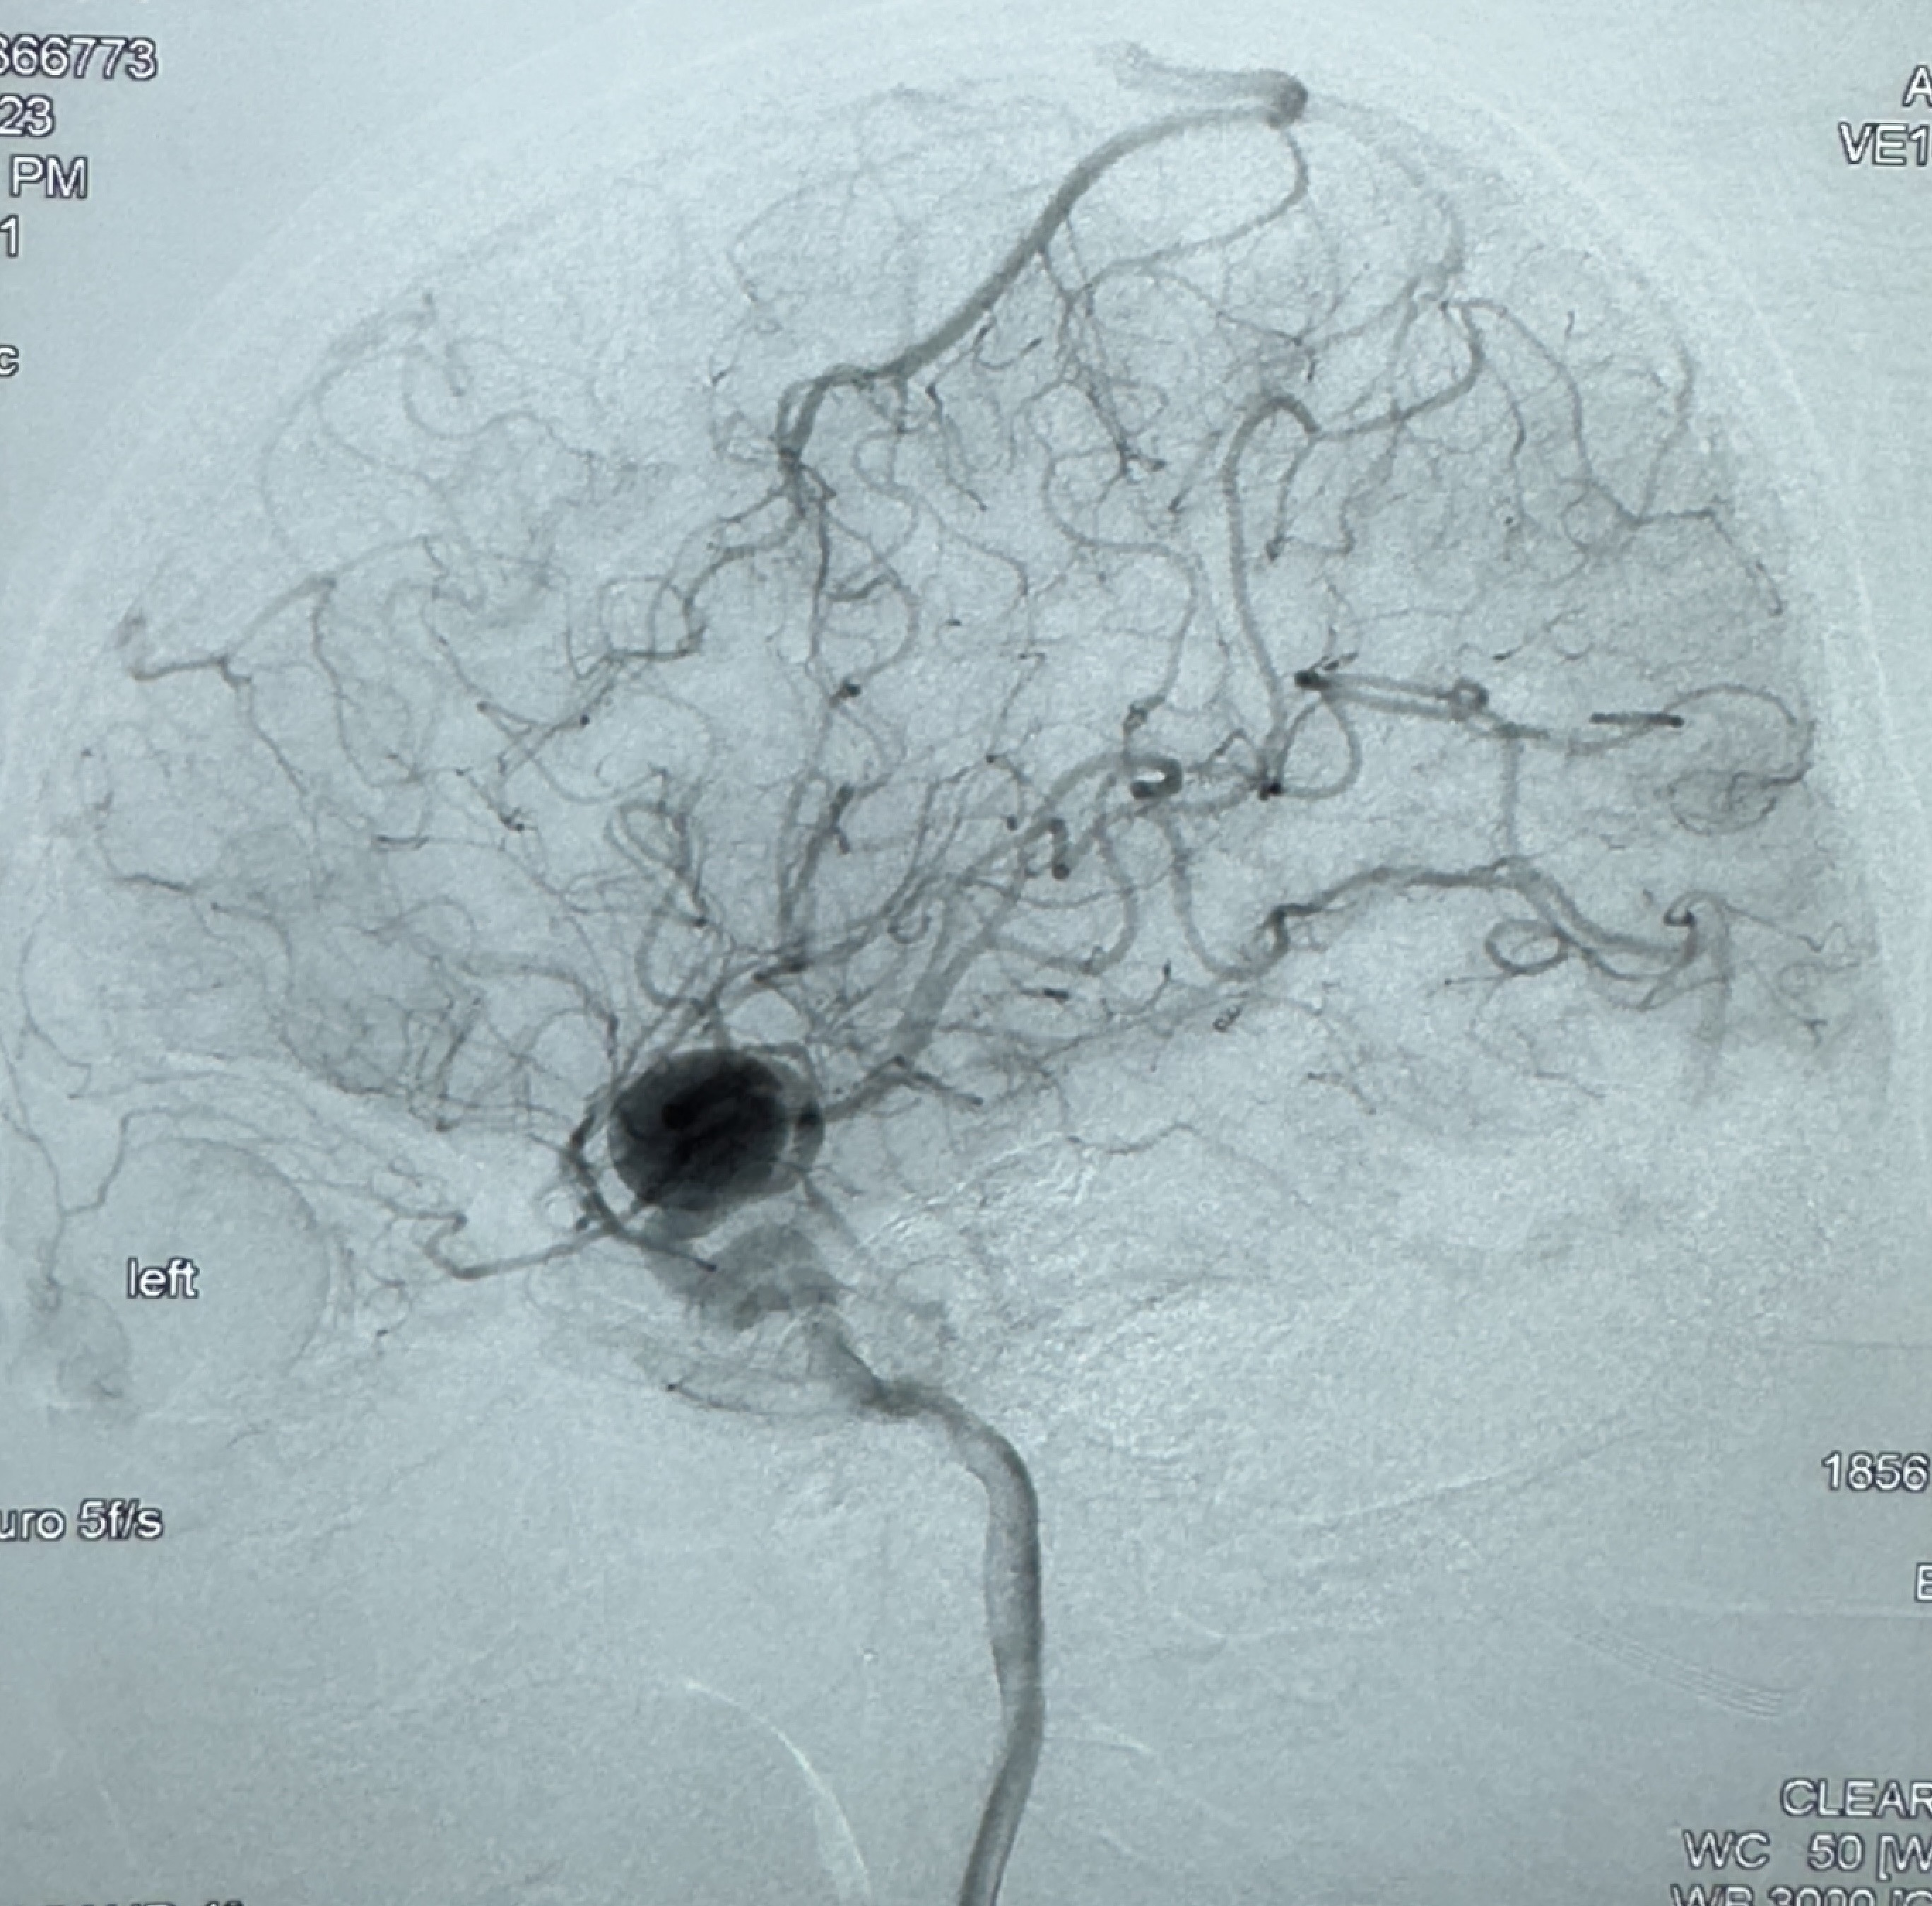

2023-12-08外院DSA:右侧颈眼动脉瘤,约13*12mm大小,压颈试验显示左右向及后向前代偿可

2023-12-18全麻下行DSA➕密网支架植入备弹簧圈辅助栓塞

2023-12-27术后第十天复查DSA

支架贴壁佳,但可见射流,咋办?